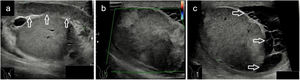

Cortes longitudinales de masas testiculares: a) Masa intratesticular homogénea e hipoecogénica (medida en ejes longitudinal y anteroposterior con línea discontinua amarilla) con diagnóstico anatomopatológico de seminoma; b) Imagen a con captación Doppler color; c) Masa que ocupa la práctica totalidad del teste (medido en ejes longitudinal y anteroposterior con línea discontinua amarilla) hipoecogénica con diagnóstico anatomopatológico de linfoma.

En varones mayores de 60 años, el tumor testicular maligno más frecuente es el linfoma, tratándose normalmente de un linfoma no Hodgkin que presenta un peor pronóstico. Suele ser en su mayoría unilateral y la ecografía nos muestra un testículo de mayor tamaño con un parénquima difusamente hipoecogénico (fig. 2c) con aumento del flujo sanguíneo, o lesiones hipoecogénicas multifocales.